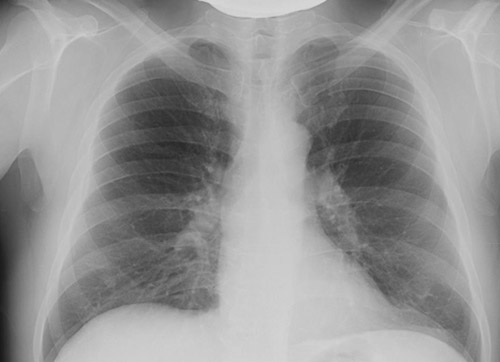

- Флюорография и рентгенография легких. Флюорография используется в качестве скринингового метода. На флюорограмме фиброз корней легких может быть замечен при бронхитах, курительном бронхите и профессиональных заболеваниях легких. Это проявляется следующим образом:

При пневмокониозах наблюдается измененный легочный рисунок, вызванный диффузным фиброзом, который имеет сетчатую или ячеистую структуру, преимущественно в нижних и средних отделах легких. Также можно увидеть линейные затемнения неправильной формы, указывающие на фиброз вокруг бронхов и сосудов. При туберкулезе в верхних долях легких отмечается сгущение и деформация легочного рисунка, возможно наличие линейного пневмофиброза, а к корню легкого уходит фиброзная дорожка. При цирротическом туберкулезе изменения фиброза преобладают над инкапсулированными очагами.

Единичный фиброзный тяж в легких, как рентгенологический признак, может быть выявлен после перенесенного воспалительного процесса (например, пневмонии или туберкулеза). Такой фиброзный тяж не представляет опасности и не влияет на дыхательную функцию, хотя его обратное развитие невозможно. Более серьезной проблемой является распространённый (диффузный) тяжистый пневмофиброз, который развивается при идиопатическом фиброзирующем альвеолите. В дальнейшем возникают диффузные изменения, проявляющиеся в виде мелкосетчатой деформации легочного рисунка.

Эти изменения имеют двусторонний характер и выражены в верхних отделах легких над диафрагмой. Характерно уменьшение объема легких, что приводит к высокому стоянию купола диафрагмы. При прогрессировании заболевания усиливаются фиброзные изменения и дыхательная недостаточность.

- Компьютерная томография с высоким разрешением (ВРКТ) является высокочувствительным методом для выявления пневмофиброза. Она позволяет оценить степень выраженности, распространенность, характер и динамику изменений. Использование тонких срезов и пространственной реконструкции значительно улучшает возможности визуализации. На ранней экссудативной стадии идиопатического легочного фиброза КТ-картина представлена затемнениями, напоминающими «матовое стекло». В дальнейшем формируются двусторонние базальные изменения, известные как «сотовое легкое», а также тракционные бронхоэктазы. Картину «сотового легкого» создают кисты размером 3-10 мм с толстыми и четкими стенками.